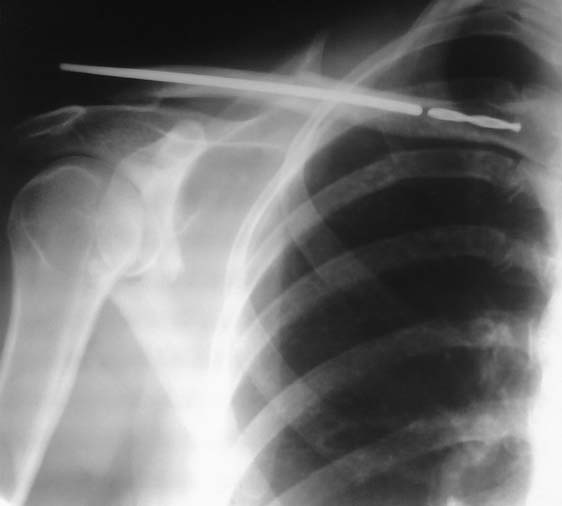

На днях прооперировали пациентку по поводу банального перелома ключицы в средней трети

сосмещением..На рентгенконтроле картинка которая представлена...Самое интересное,что

не заметили момент когда оставили кончик сверла при рассвсверливании под богдановский

стержень,ни я не ассистент,ни операционная сестра...Сейчас,рана заживает первичным

натяжением.Жалоб нет. Какие варианты в дальнейшем?Пытаться удалить при удалении

стержня?Или как предлагают "оставить на память"? Прошу прощения за качество снимка,делали